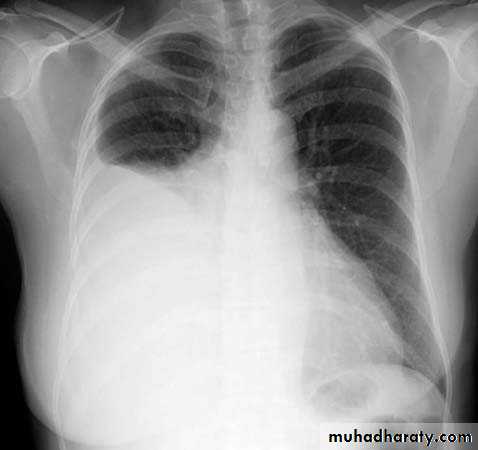

Homogenus opacity of the left hemithorax with shifting of the trachea to the same sidePleural effusion

Homogenus opacity of right lower zone with meniscus signOblitration of right cardiophrenic and costophrenic angles

Homogenus opacity of the right hemithorax

Oblitration of cardiophrenic and costophrenic angles

Shifting of the trachea to the opposite side

Pleural effusion

Homogenus opacity of right lower lobe with Oblitration of right cardiophrenic and costophrenic angles.

Meniscus sign